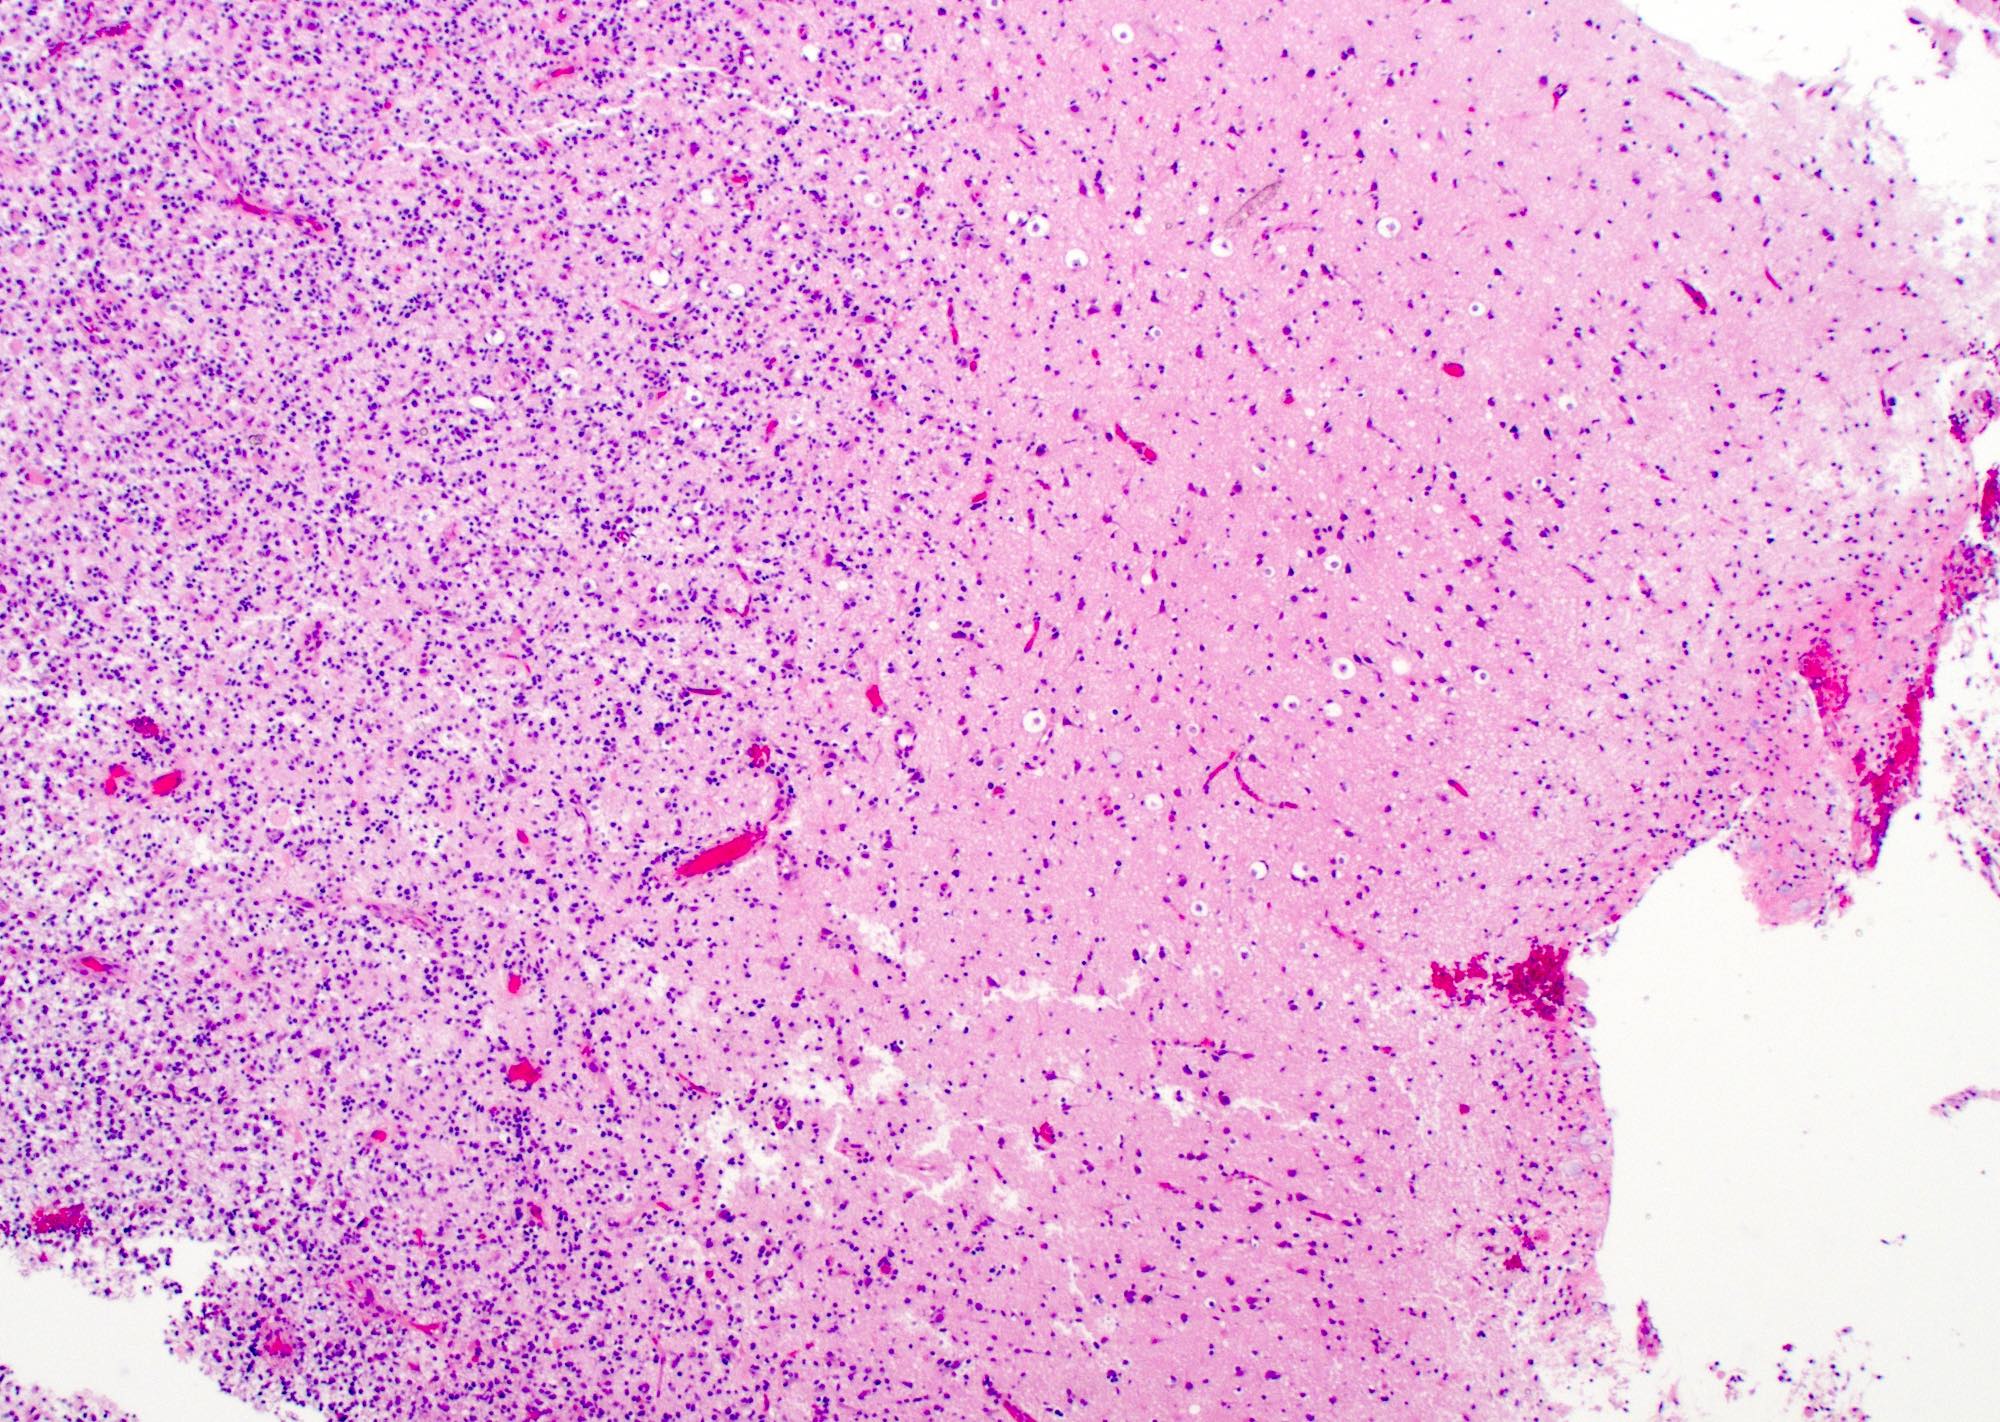

Microscopic (histologic) description

- Infiltrating, hypercellular astrocytic neoplasm often with hyperchromatic, elongated nuclei and irregular nuclear membranes

- Microvascular proliferation or necrosis is required for a histologic diagnosis of GBM

- Microvascular proliferation: multilayered, small caliber vessels with glomeruloid appearance (J Neuropathol Exp Neurol 1992;51:488)

- Necrosis: can be geographic or pseudopalisading with neoplastic cells surrounding central necrosis

Microscopic (histologic) images

Contributed by Bharat Ramlal, M.D. and Meaghan Morris, M.D., Ph.D.